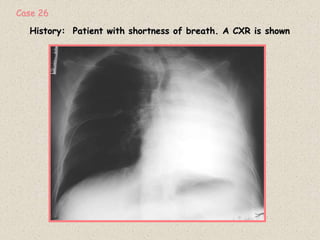

History: Patient with shortness of breath. A CXR is shown

Case 26

RADIOGRAPHIC FINDINGS:

1: Total opacification of left hemithorax

2: Shift of mediastinum to the left

DIFFERENTIAL DIAGNOSIS

1: Collapse of lung due to endobronchial obstructing lesion

2: Previous total pneumonectomy

A CT scan was done shown below

Diagnosis:

Complete collapse of Left lung.

Etiology: Large bronchogenic carcinoma